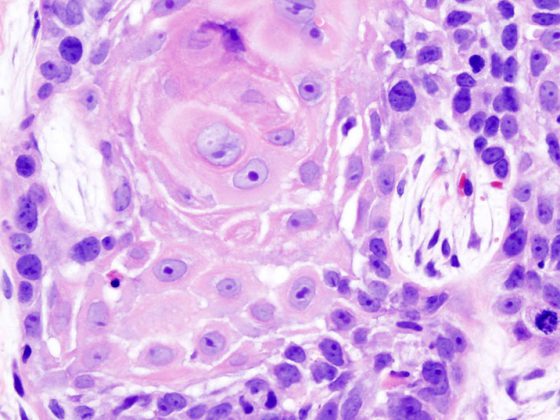

plattenepitelkarzinom_wikimedia

Spinaliome können auch aus frühen aktinischen Keratosen entstehen